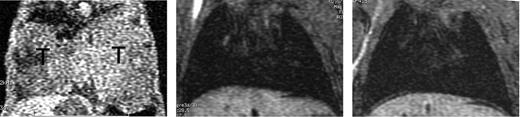

To determine whether the transfection of IL-15Rα on MC38 cells resulted in the loss of fatal pulmonary metastasis formation, we examined lungs of those mice by MRI. While all mice (n = 11) that received wild-type MC38 displayed massive growth of MC38 cells in their lungs (Figure 6A), no apparent pulmonary metastasis were detectable in mice injected with both high and moderate IL-15Rα+ MC38 cells (Figure 6B-C). Curiously, mice (n = 5) that were injected with IL-15Rα+ (moderate) MC38 cells developed palpable metastatic tumors in the peripheral and internal lymph nodes (see “Discussion”), which may be responsible for the death of nearly half of the mice that received the injection of IL-15Rα+ (moderate) MC38 cells. These results indicate that the expression of IL-15Rα on MC38 cells efficiently prevented fatal pulmonary metastases of MC38 cells in immune-competent wild-type C57BL6 mice, leading to the prolonged survival of the host. Overall, the in vivo observations seem to correlate well with the highly augmented killing activity of NK cells as a consequence of the IL-15 trans-presentation by IL-15Rα+ MC38 cells in vitro.

No pulmonary metastasis in C57BL/6 mice injected with IL-15Rα–transfected MC38 cells. Micro-MR images of lungs of C57/BL6 mice injected with parental or IL-15Rα–transfected (high or moderate expression) MC38 cells are shown. Parental MC38 cells formed fatal pulmonary metastases and almost filled the lungs of all of the injected mice (n = 11) (left). In contrast, no visible metastatic masses were observed in lungs of all mice (n = 6) injected with IL-15Rα+MC38 (images were taken at 28 days after injection; T indicates tumor).